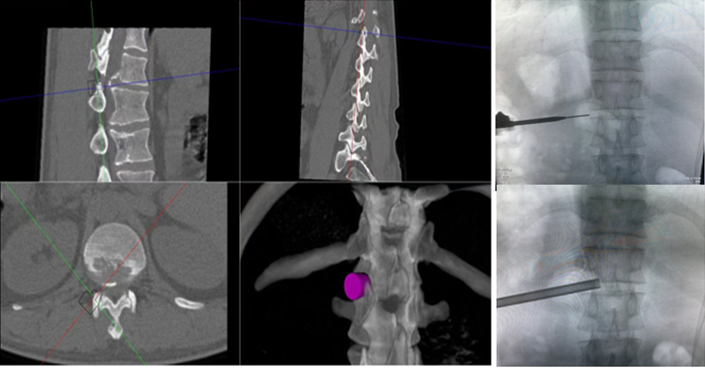

ORTHBOT脊柱机器人术前设计及术中穿刺